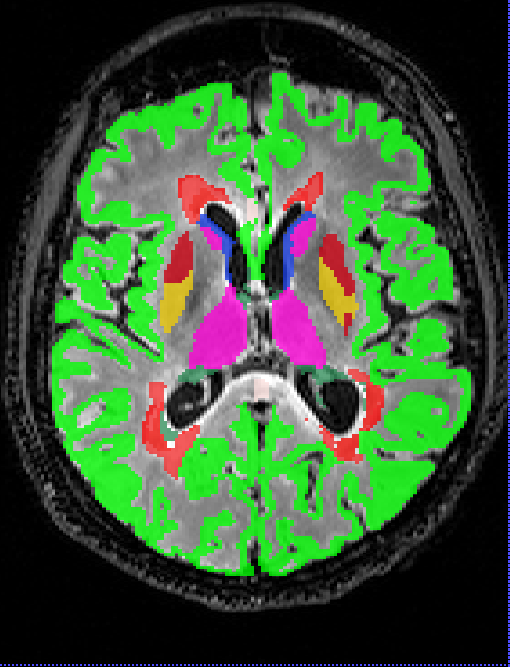

Box plots of the Dice coefficient for the segmentation (DeepSCAN multi-task) of various grey matter structures, when compared with Freesurfer, can be found in Figure 3. Both models performed quite robustly when applied to the Insel32 dataset. However, the nnUnet model can be seen to make substantial errors in the placing of structures on the MSSEG (out of sample) dataset, as can be seen in Figure 4.